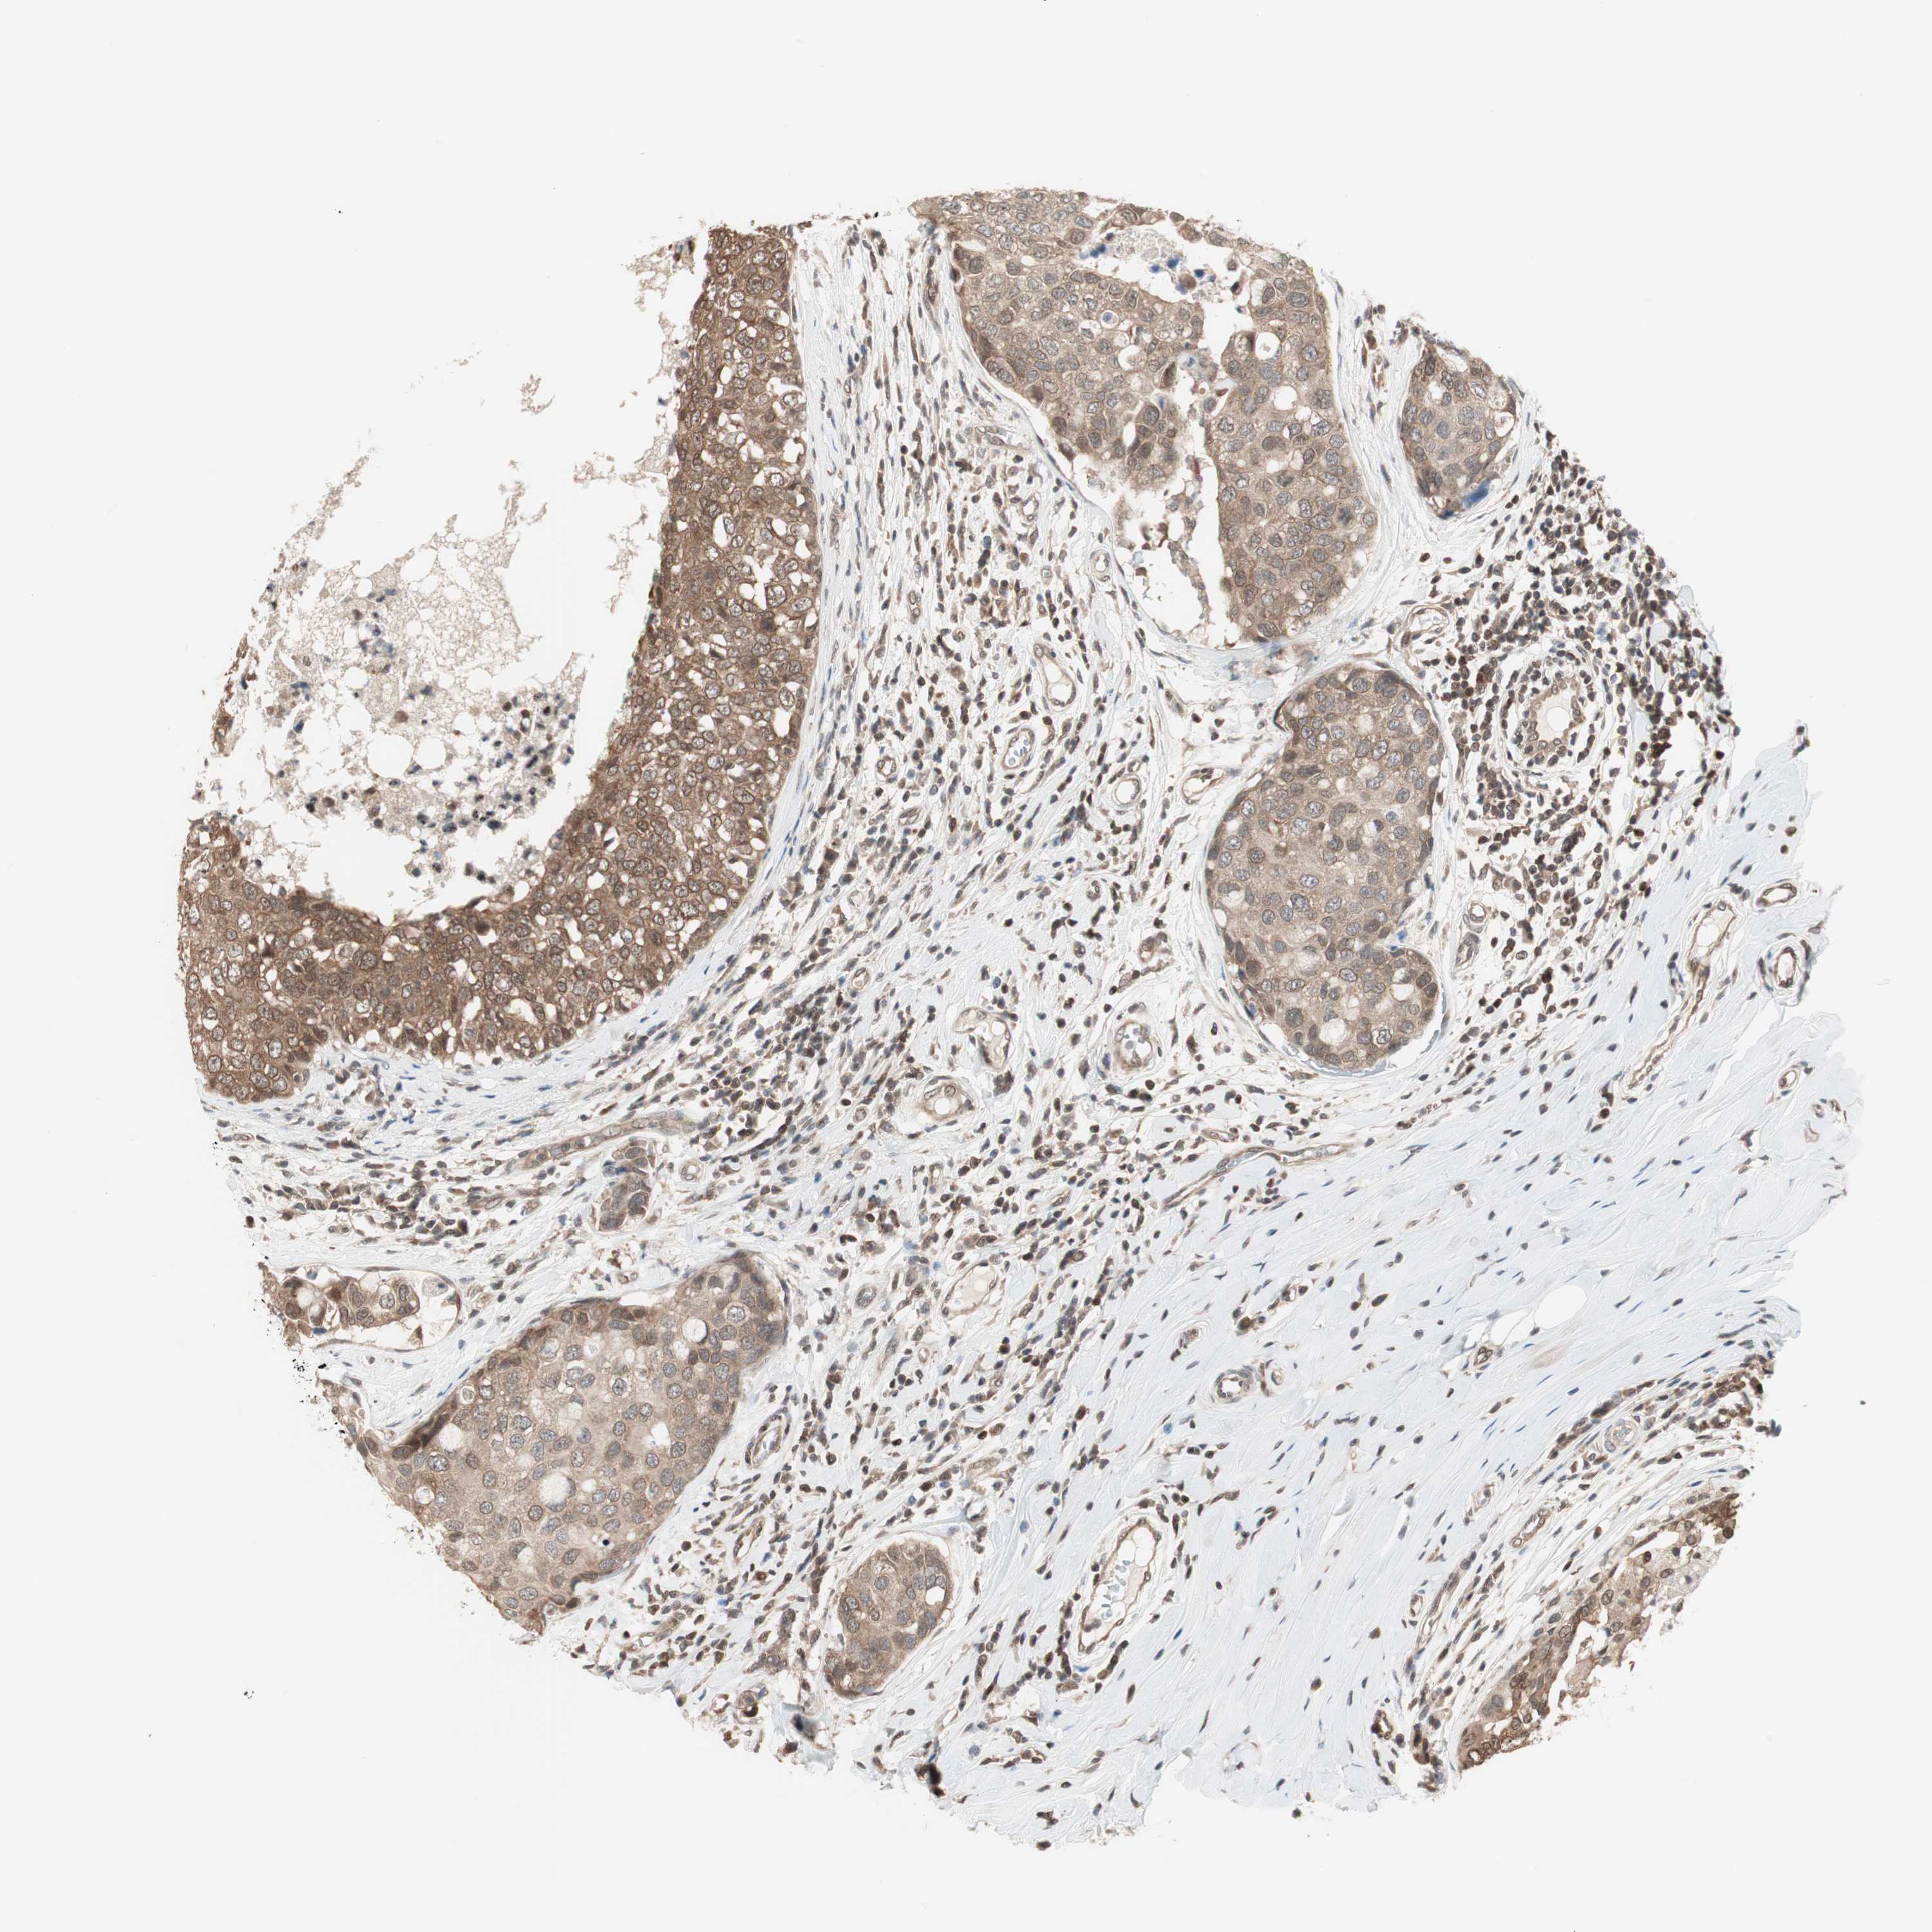

CANCER BREAST CANCER Show tissue menu

BRCA TCGA BRCA VALIDATION PROTEIN EXPRESSION